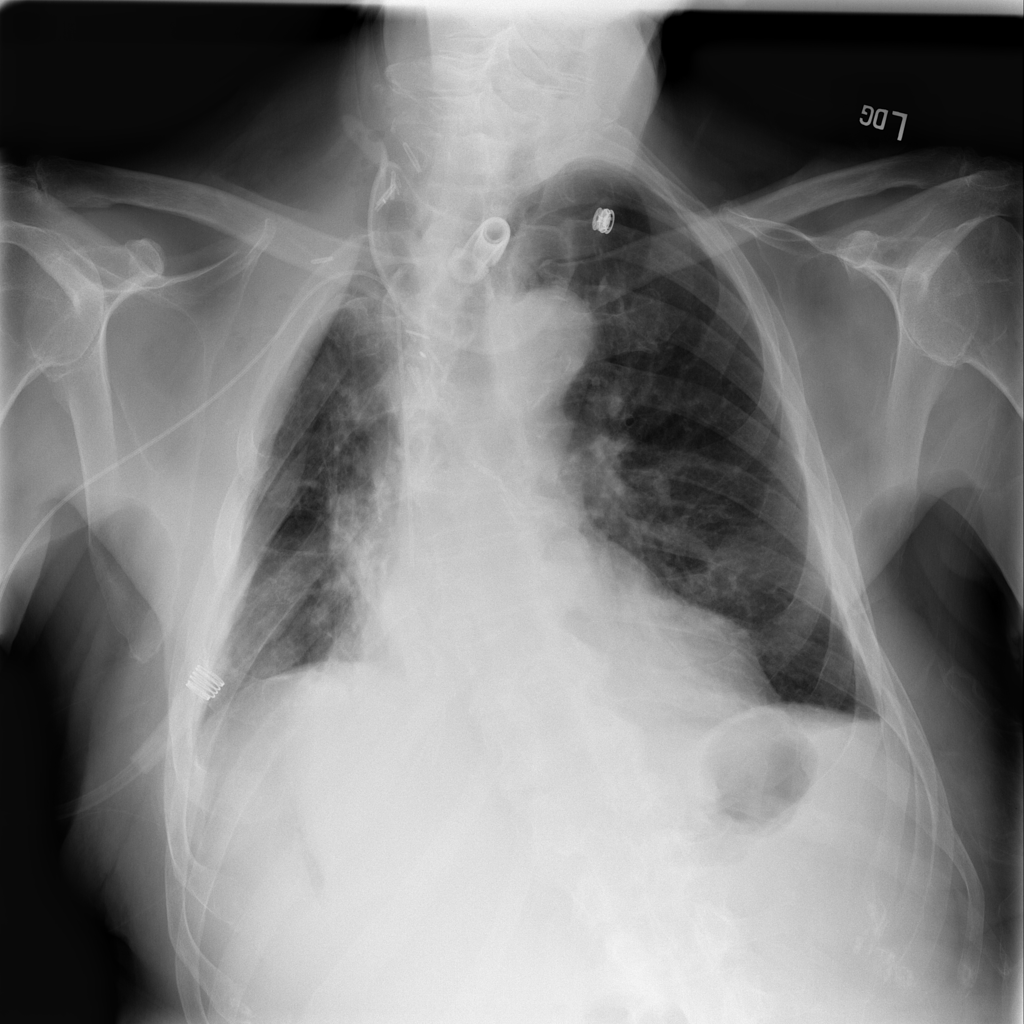

PAT-50E5 · IMG-008Mass

PAT-50E5 · IMG-008

PA